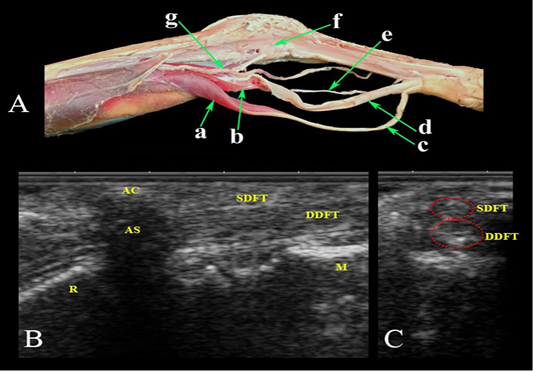

Palmar aspect of the carpal region. (A) Photomacrograph of the deep dissection of the forearm region and carpal canal. Ultrasonographic imaging: (B) LS and (C) TS. a- Superficial digital flexor M.; b- Deep digital flexor M.; c- Superficial digital flexor tendon; d- Deep digital flexor tendon; e- Median Nerve.; f- Carpal canal opened; g- Median Artery; AC- accessory carpal bone; AS- Acoustic shadow; SDFT- Superficial digital flexor tendon; DDFT- Deep digital flexor tendon; R- Radius; M- Metacarpus.